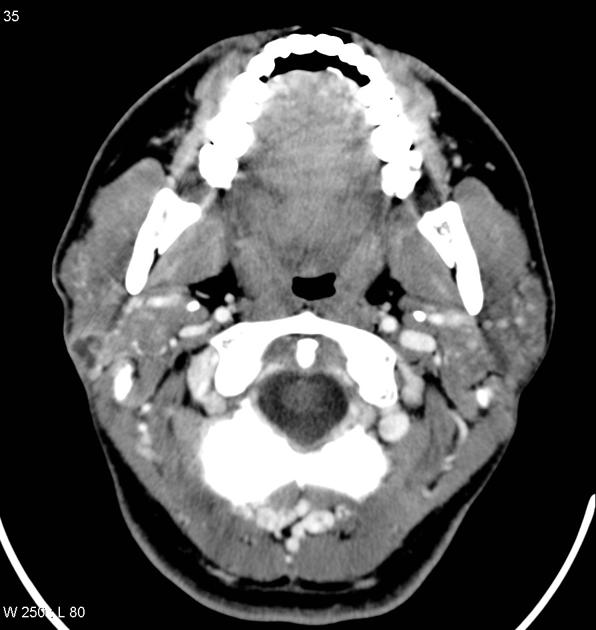

- Grossly:

- The tumor is poorly circumscribed

- Measures from 3 to 5 cm